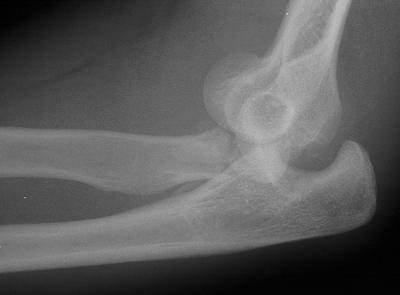

Injury:

Elbow fracture dislocations present a variety of problems. Instability with recurrent anterior subluxation can arise when the injury destroys both the radial head and the coronoid buttress. In this case, the patient sustained an elbow fracture-dislocation with a comminuted radial head fracture and 50% coronoid fracture.